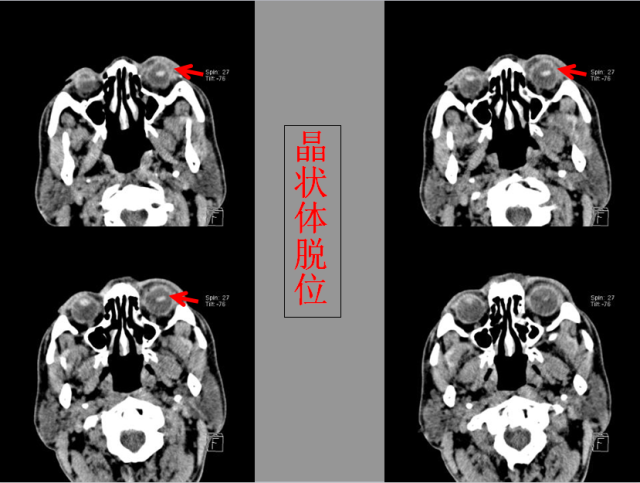

定义:关节脱位是暴力、关节感染、附近软组织挛缩或先天骨发育障碍造成的关节对位关系部分或完全脱离,即为半脱位或脱位。临床上以创伤性脱位*常见。